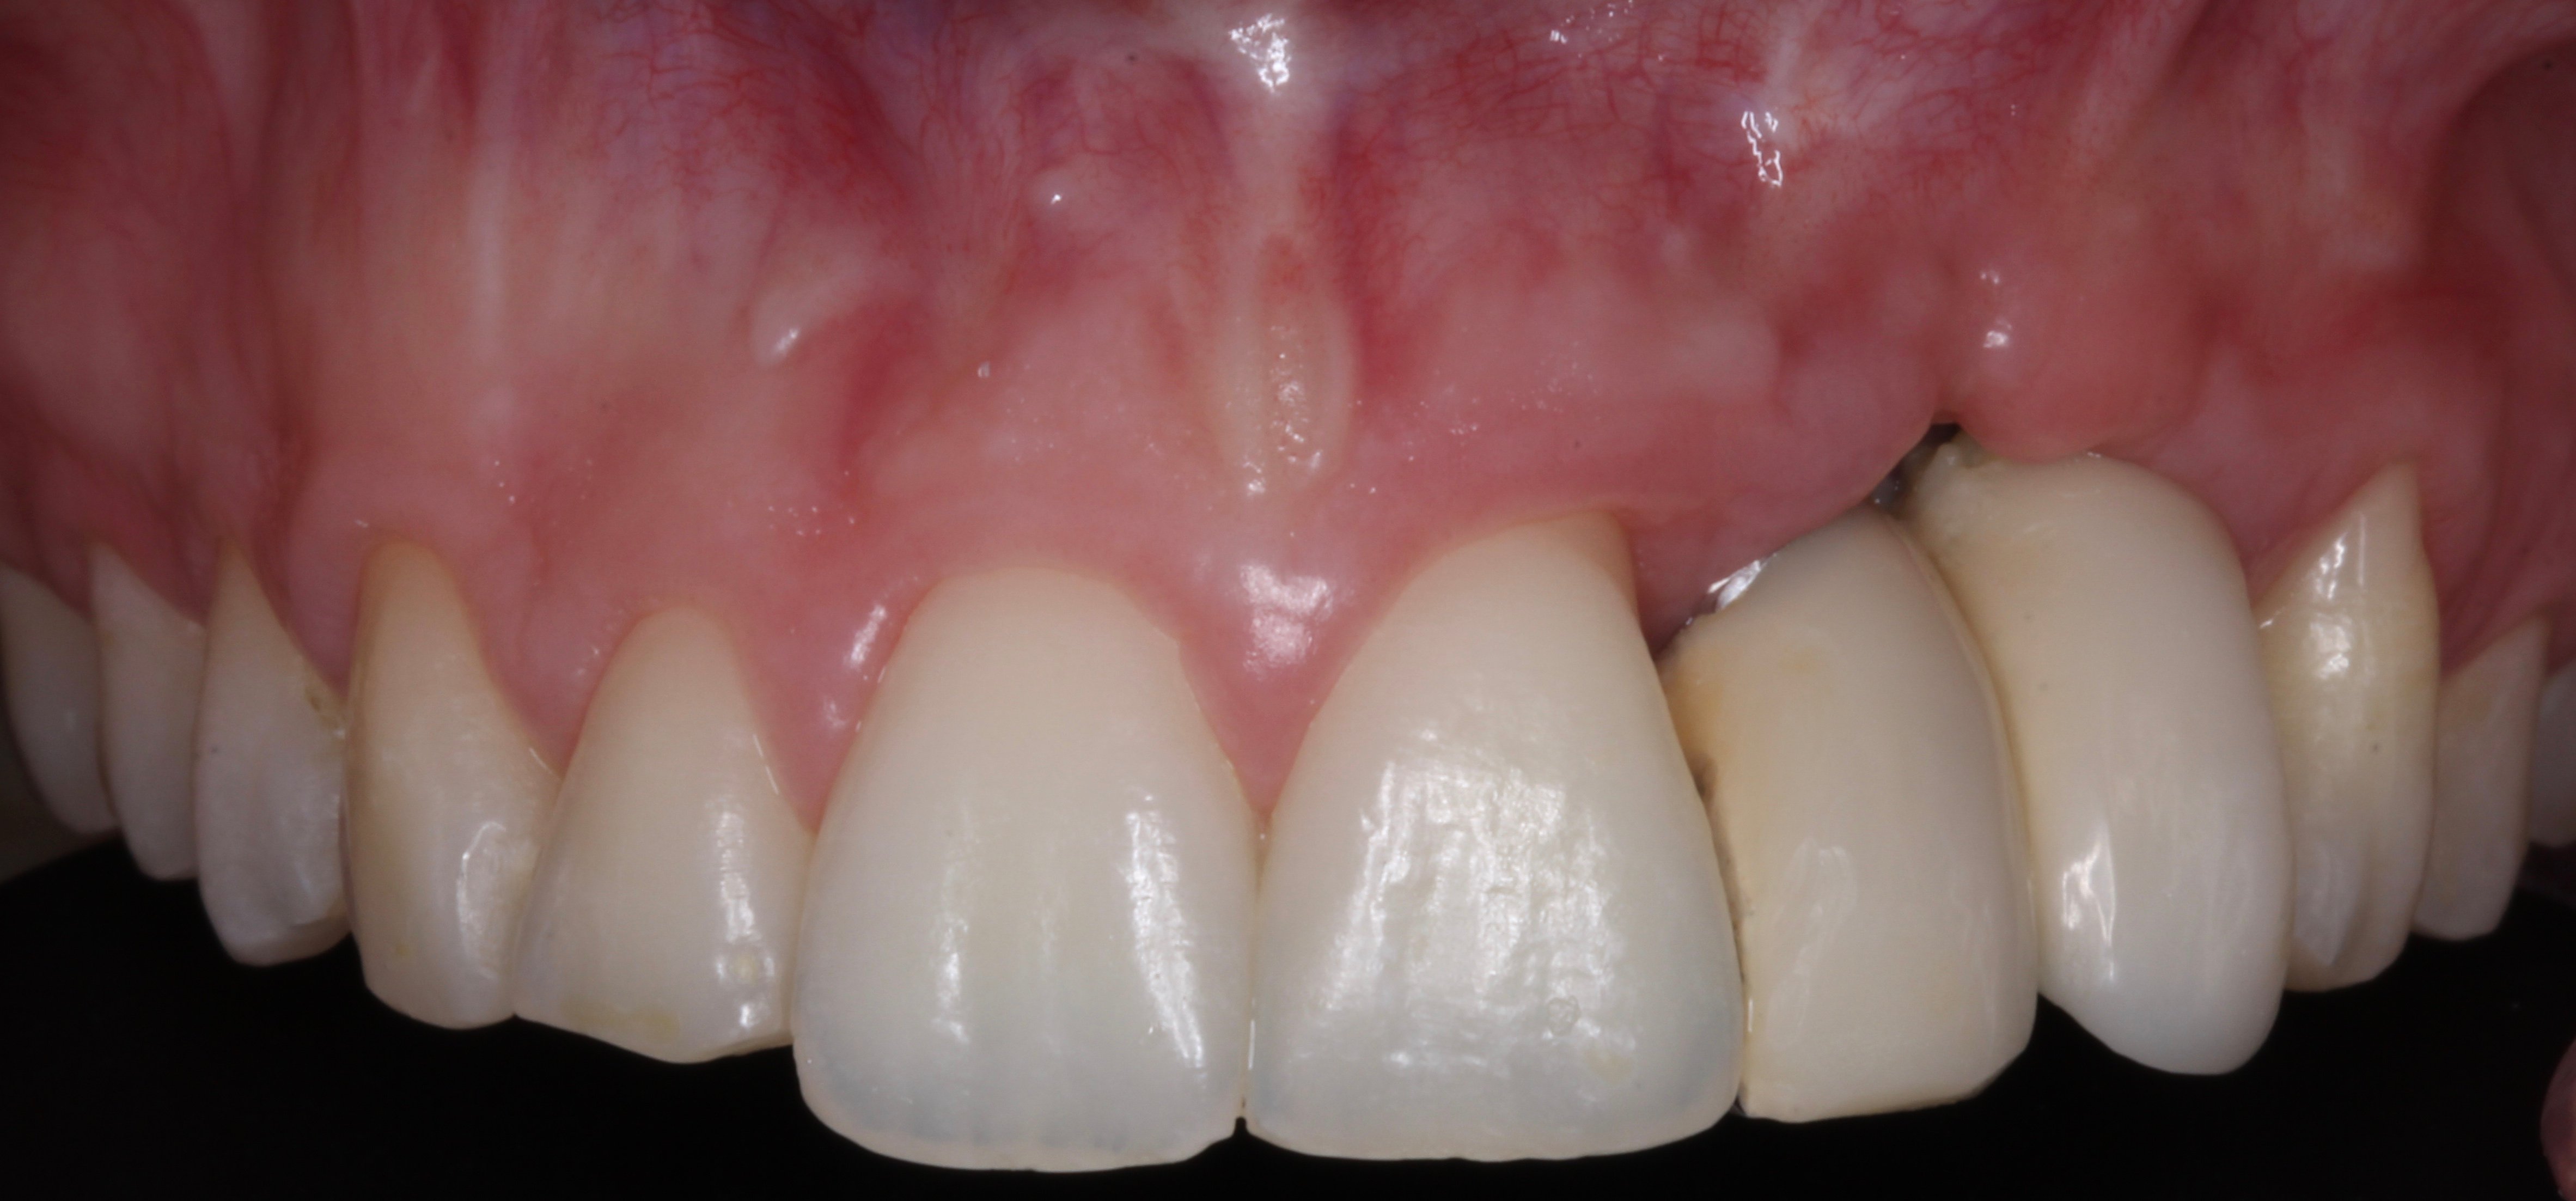

- 4 years later: Clinical and Radiographic Evolution of the Aesthetic Zone.

3D guided bone regeneration using an e-PTFE, Ti-reinforced NeoGen® membrane and 100% autogenous bone is a fully predictable treatment for the severe hard and soft tissue atrophy on the Aesthetic Zone. This statement is supported not only by panoramic and periapical x-rays, but also by CBCT sectional cuts where we can see the complete stability of the regenerated bone.